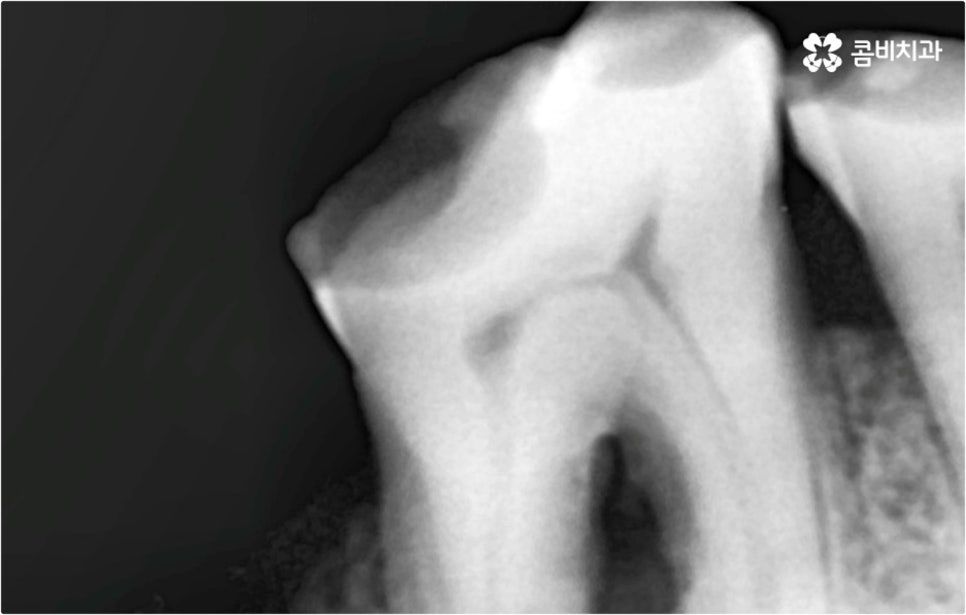

특히 한 두 개가 아니라 대부분의 치아를 잃게 되었을 때는 식사를 할 때 문제가 생겨 살아가는 데 필요한 영양소를 제대로 공급받지 못할 가능성이 높아질 뿐 아니라 장기적으로 소화 불량, 위장 장애 등을 겪을 수 있어요. 잘 씹지 못하면 치매에 걸릴 수 있다는 연구 결과도 있기 때문에 무심하게 넘어가시면 안 될 거예요. 또한 치아 상실을 오랜 시간 방치하면 잇몸뼈가 흡수되고 주변 치열이 쓰러지는 등 교합이 어긋날 수 있으며 얼굴 균형이 달라지는 등 심미적으로도 좋지 않은 영향을 받을 수 있어서 될 수 있는대로 빨리 이를 대체해 주실 필요가 있어요.

예를 들어 사고를 통해 한꺼번에 여러 개의 치아가 부러지거나 빠진 경우 연령 또는 전신 질환 여부 등을 살펴보고 치조골 상태가 양호하다면 보다 빠르고 간편한 당일 식립 방식을 이용해 볼 수 있어요. 그러나 하나 둘씩 치아가 빠질 때 마다 제때 치료를 해 주지 않아 치료 시기를 놓치고 결과적으로 무치악 상태에 이른지 오래 된 경우 또는 틀니를 오래 착용하여 잇몸뼈가 이미 많이 내려앉은 경우라면 바탕이 되는 잇몸뼈를 보충해 준 후 식립을 진행하는 방식을 이용해야 할 거예요.

임플란트 수술 후 발생할 수 있는 혹시모를 부작용 중 가장 대표적인 것은 주변 잇몸에 염증이 생기는 거예요. 임플란트 치아는 구조상 자연 치아와 다르게 자연스럽게 움직이면서 충격을 흡수하는 치주 인대가 없는 만큼 갑작스럽게 큰 힘이 가해질 수 있는 너무 딱딱한 음식을 씹으면 잇몸에 부담이 가서 피가 나거나 부어 오를 수 있으며, 주변 위생을 청결하게 유지하지 않으면 세균이 증식하여 염증이 생길 수 있으니 항상 잇몸 건강 상태를 양호하게 관리하는데 신경쓰실 필요가 있어요.